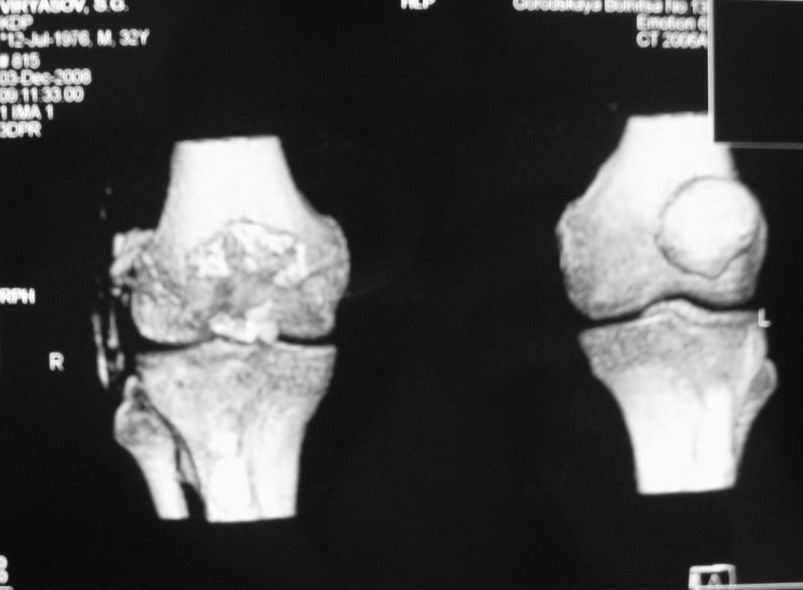

Уважаемые коллеги! Обратился пациент 32 лет с травмой коленного сустава от июля 2008 года - падение с мотоцикла, прямой удар передней поверхностью коленного сустава. Диагноз - открытый оскольчатый перелом надколенника. В одной из больниц города выполнили ПХО, шов надколенника лавсаном. Заживление раны с частичным нагноением(разведена на участке 3 см).Сейчас мягкие ткани в порядке. R-снимки, КТ в приложении. Объем движений 0/0/110 гр.Ходит почти без хромоты. Жалобы на торчащий под кожей один из отломков, боль в этой точке. Вопрос: что делать? Первое - убрать этот отломок и на этом закончить. Второе - оставить все как есть(отломок не так уж и сильно мешает). Ждать возможного развития артроза, дальше по ситуации. Третье - подумать о протезировании надколенника.

Внешний вид коленного сустава